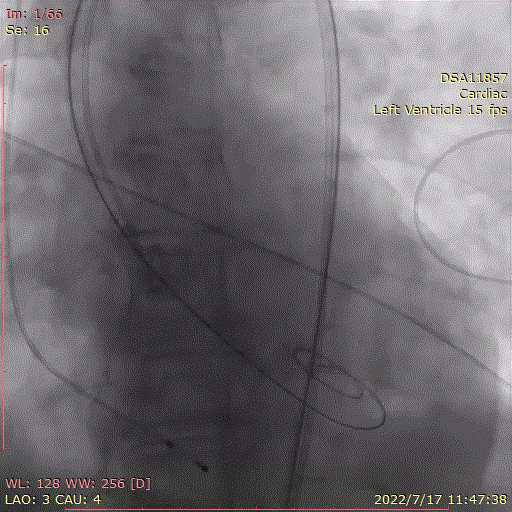

主动脉根部造影示主动脉瓣重度狭窄,采用20mm球囊预扩,有轻微腰征,无造影剂渗漏。

主动脉根部造影

直头导丝跨瓣

20mm球囊预扩张